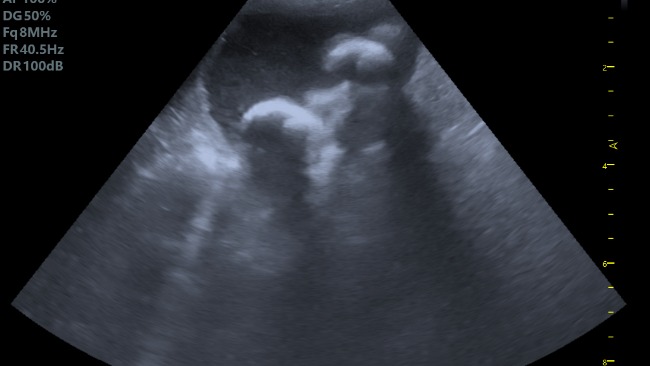

Jest to suczka i nazywa się Fifi, ma 12 lat i okazało się że ma kamicę (kamienie na pęcherzu które są duże i jest ich wiele). Fifi potrzebuje zabiegu i przygotowania do niego. Trzeba zrobić także niezbędne badania krwi plus podstawowe do zabiegu a także trzeba liczyć się z kosztami wizyt kontrolnych. Mnie samej poprostu na to nie stać, a moja suczka się męczy. Nie pozwólmy odejść jej za tęczowy most.

Proszę o pomoc gdyż wiem że sama nie jestem w stanie pomóc mojej Fifi. Jest ona dla mnie bardzo ważna a ma jeszcze trochę życia przed sobą. Oczywiście dodaję ostatnie badania mojej Fifi.